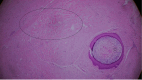

Background: This case report highlights a rare instance of concurrent keloid and epidermal cyst development at an ear cartilage harvest site following rhinoplasty in a 25-year-old woman. Both conditions, which typically stem from skin trauma, seldom occur together, demonstrating the exceptional characteristics of this case.

Case summary: The patient underwent successful surgical removal of both the keloid and the epidermal cyst. Postoperative treatment included the use of silicone sheets, gel, and oral tranilast to reduce scarring. No recurrence was observed over a 6-mo follow-up period, indicating effective management of the condition.